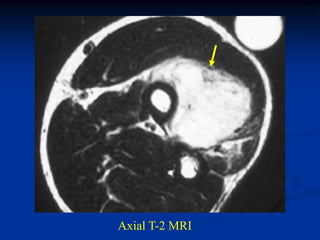

CLASSIC    Case #266   Axial T-2 MRI

41 year male

fibrosarcoma

forearm

Coronal T-2 MRI

Axial T-2 MRI